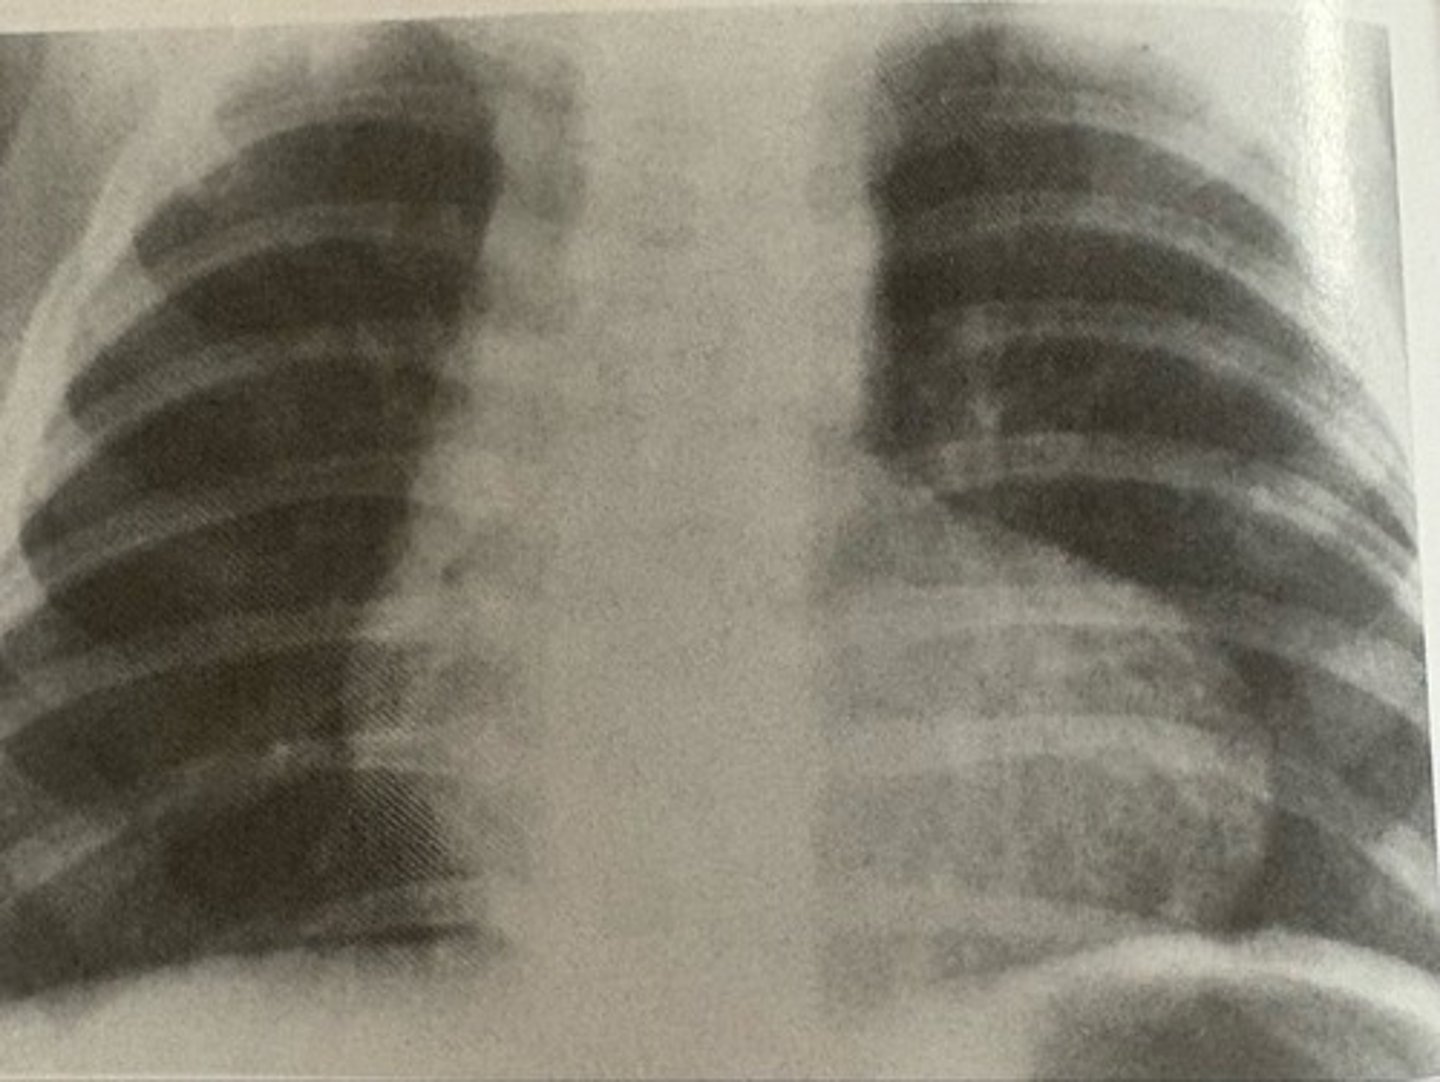

Teratology of Fallot

what pathology is present?